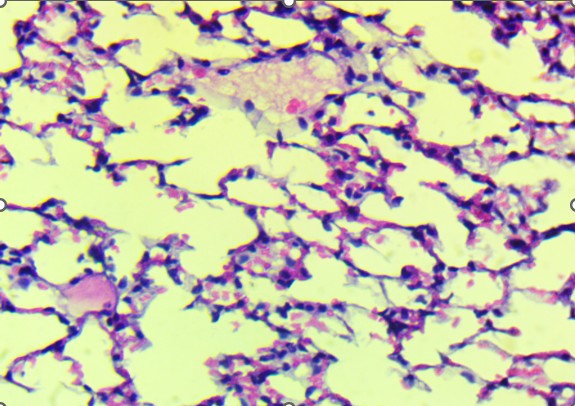

In the mid-dose group (0.7 mg/kg), histopathological changes became more apparent. The alveolar septa were mildly thickened, and there was evidence of focal inflammatory infiltration, particularly in the peribronchiolar regions. These findings suggest early-stage toxic alveolitis, possibly mediated by oxidative or inflammatory mechanisms triggered by the plant’s alkaloids. The high-dose group (4 mg/kg) revealed the most prominent pulmonary lesions.

Bronchiolar epithelium appeared partially detached, and several lung sections displayed eosinophilic proteinaceous material within the airway lumens. Alveolar spaces were noticeably reduced, and focal hemorrhages were present, indicating increased capillary permeability or endothelial injury (Figure 3).

|

A. Control: Normal alveoli and septa. |

B. T1: Comparable to control with minimal epithelial irregularities. |

C. T2: Septal thickening and peribronchiolar infiltration. |

D. T3 epithelial detachment. |

E. T3 intra-alveolar hemorrhage. |

F. Representative treated: Multifocal hemorrhage and inflammation. |

Figure 3. Lungs of Swiss albino mice: (A) Control with intact alveoli, (B) T1 minimal changes, (C) T2 septal thickening, (D) T3 epithelial detachment, (E) T3 intra-alveolar hemorrhage, (F) Representative treated lung with multifocal hemorrhage.

Despite the severity of these findings, there was no widespread consolidation or fibrotic remodeling, implying that the damage remained in the acute, potentially reversible phase. Animals from the recovery group that received the high dose followed by a treatment-free period showed partial resolution of pulmonary lesions. While some inflammatory features had regressed, mild septal thickening and epithelial irregularities persisted, indicating incomplete histological recovery within the observation window.

In contrast to the heart, the lungs exhibited apparent dose-related histological alterations (Figure 3). In control animals (Figure 3A), pulmonary tissue appeared intact with open alveolar spaces, thin interalveolar septa, and unremarkable bronchiolar epithelium. This structure was mainly preserved in the low-dose group (Figure 3B), with only minor irregularities. However, lungs from the mid-dose group (Figure 3C) began to show mild septal thickening and peribronchiolar inflammatory infiltration, indicating the onset of localized alveolar injury.

At the highest dose (Figures 3D and 3E), the lung tissue revealed more severe pathology, including bronchiolar epithelial detachment, eosinophilic deposits, reduced alveolar spaces, and focal hemorrhage. These findings suggest a toxic alveolitis-like response, potentially driven by a combination of muscarinic receptor blockade, which can impair airway regulation and mucosal secretions, and oxidative stress, which may provoke capillary leakage and inflammatory activation. Similar histological patterns have been reported in experimental and forensic studies of acute Datura intoxication, often correlating with respiratory distress or pulmonary edema observed at autopsy (Boumba et al., 2004; Le Garff et al., 2016; Shifa et al., 2024).

Of particular interest, lungs from recovery animals (Figure 3F) showed partial resolution of lesions. Although inflammation was reduced and some epithelial reorganization had occurred, residual septal thickening persisted, indicating that while some of the extract’s pulmonary effects are reversible, complete histological recovery may require a more extended withdrawal period or additional therapeutic support. This partial reversibility aligns with clinical cases in which respiratory symptoms improve following cessation of exposure and supportive care.